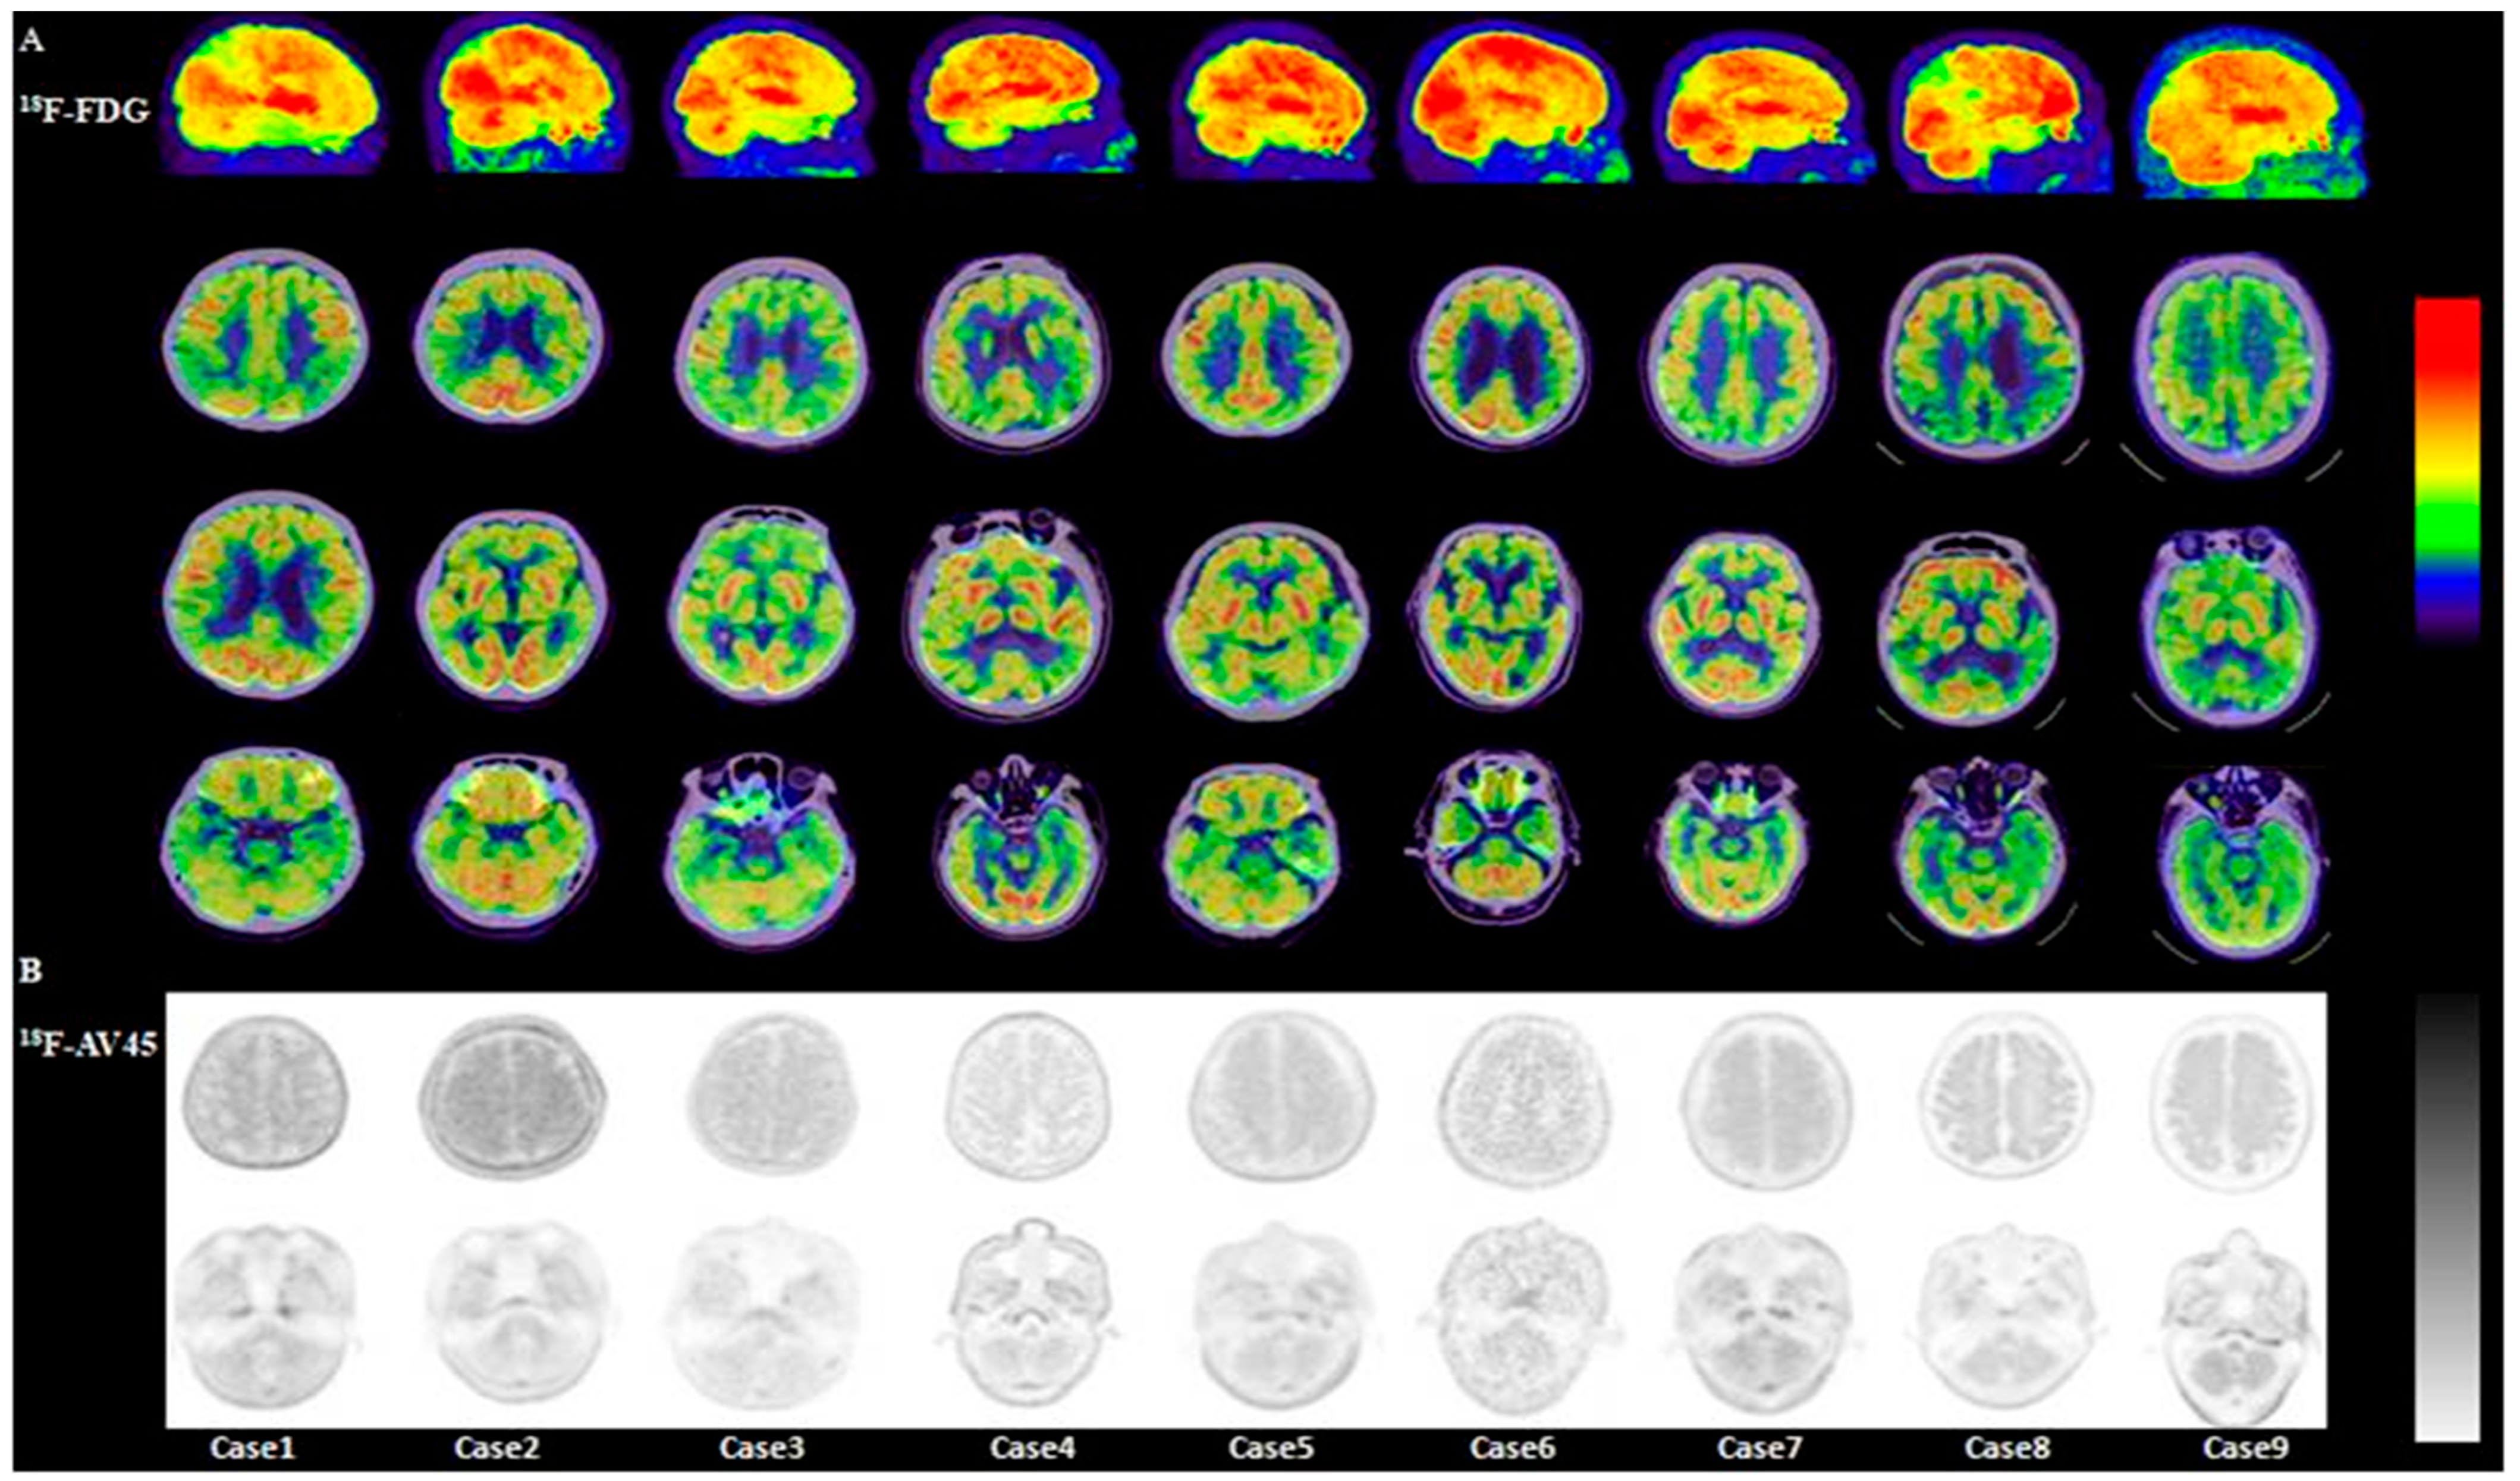

3.2.1. Visual Analysis of 18F-FDG PET/CT

3.2.4. Visual Analysis of 18F-AV45 PET/CT

3.2.5. Semi-Quantitative Analysis of 18F-AV45 PET/CT